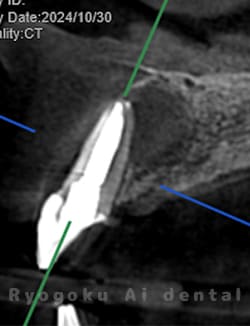

Case14

-

術後半年レントゲン

- 原因

- 左上1、2番歯根嚢胞

- 治療内容

- 歯根端切除法

- 治療費用

- ¥77,000×2

前歯の違和感が治らず、他院では治療を断られたとのことでご来院された患者様です。左上1、2番に口蓋側まで及ぶ嚢胞が存在したため、歯根端切除術を行いました。経過良好です。